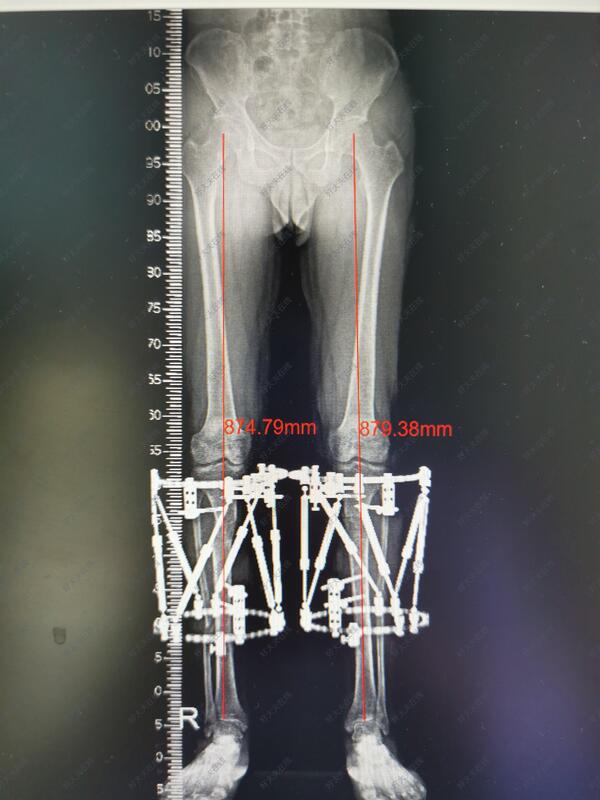

内翻膝关节炎治疗

治疗前

年轻的内翻膝关节炎,往往体现为运动后膝关节疼痛,愿意接受手术治疗的,将来往往可以避免年纪大的时候关节疼痛,从而避免关节置换手术

治疗中

六轴空间矫形支架具有调节精准准,病人可以早期负重